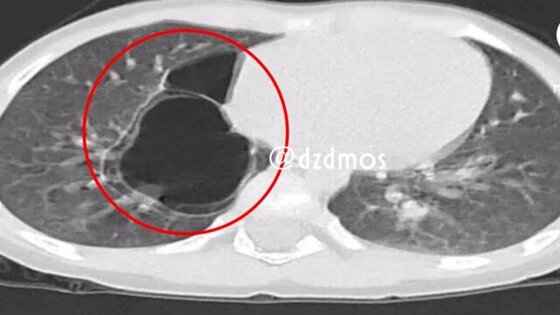

Рентген выявил уплотнения в правом легком, а компьютерная томография позволила установить точный диагноз – врожденную кистозно-аденоматозную мальформацию легких.

При таком нарушении здоровая легочная ткань замещается аномальной, что приводит к образованию кист. Со временем они увеличиваются и могут вызывать дыхательную недостаточность и тяжелые воспалительные осложнения.

Как пояснил детский хирург отделения № 2 Ампар Фатима, с помощью специального инструмента были извлечены два тонкостенных кистозных образования диаметром до 6 и 3 сантиметров, внутри которых находились дополнительные мелкие кисты.